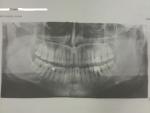

Pomka. Опубликовано 23 мая, 2012 Опубликовано 23 мая, 2012 давайте хвалится у кого какие есть снимки. выкладываем только своё. вот я не поленился и сходил 21 мая сделал вам свою улыбку

Sandynist Опубликовано 23 мая, 2012 Опубликовано 23 мая, 2012 (изменено) Роман, скажи пожалуйста, а что у тебя за навороты на нижней правой шестёрке? Такое диковинное сооружение! Даже себе такое захотелось (Если я правильно понял, то там торчит 2 штифта, и сверху ещё нагромождение керамики?) Ну и моя фотка, строго конфиденциально! За пределы форума не выносить! Изменено 23 мая, 2012 пользователем Sandynist

Zaitsev Oleg Опубликовано 23 мая, 2012 Опубликовано 23 мая, 2012 вот я не поленился и сходил 21 мая сделал вам свою улыбку Один из зубов нужно лечить

Sandynist Опубликовано 23 мая, 2012 Опубликовано 23 мая, 2012 (изменено) Семёрка правая нижняя - явный баг, межзубное повреждение. Изменено 23 мая, 2012 пользователем Sandynist

Pomka. Опубликовано 24 мая, 2012 Автор Опубликовано 24 мая, 2012 (Если я правильно понял, то там торчит 2 штифта, и сверху ещё нагромождение керамики?) угу коронка на штифтах сидит а под ним тухляк полный тёмное пятно. да и правее с боку дырка образовалась судя по фотке. Один из зубов нужно лечить как минимум два тот что с коронкой сказали строго на удаление так как под ним черное пятно типа кость стухла и потом протез ставить вот ищу хорошего мастера по зубам. а то тут в мастердент фотку сделал проконсультировался и бежать от туда...цены у них пипец... 5000 руб вырвать...30000 руб протез и это ещё не считая заморозки и всякие костные закладки для протеза...минимум тысяч на 50000 руб.